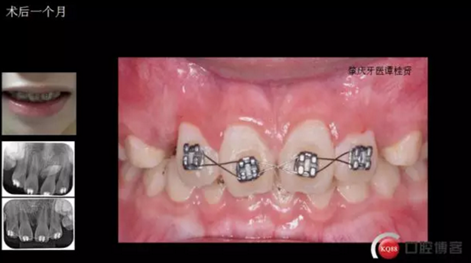

確定了方案和術(shù)前良好溝通和小孩良好的配合,牙齒很快就拔了出來。

年輕就是優(yōu)勢,牙齦長得非??旆浅:茫?/p>

術(shù)后思考:患兒如今已經(jīng)十一歲多, 雖然已經(jīng)給尖牙騰出了位置,然而全景片顯示兩顆尖牙位置依然很深,是主動出擊還是靜觀其變呢?歡迎大家共同探討!